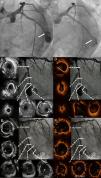

Coronary CT scan aneurysm characterisation. A) LCx maximum pixel intensity multiplanar reconstruction or MIP-MPR. B). Cardiac 3D volume rendering oriented like cranial RAO showing LCx and aneurysm. C) 3-month-follow-up coronary CT scan. LCx centreline curved multiplanar reconstruction. D) LCx 3D rendering. E) LCX straight line reconstruction derived from curved centreline. MPR (so called virtual IVUS). Axial images (red mark) revealing the stent.

Case ReportA 66-year-old male ex-smoker with hypertension, type 2 diabetes mellitus and dyslipidaemia, without history of trauma, vasculitis or connective tissue disorders, was admitted due to a non-ST segment elevation myocardial infarction with mild troponin I elevation (Grace 2.0: 93; estimated 1-year mortality 3.1%; estimated 3-year mortality: 7.1%; Crusade: 27, 6.1% bleeding risk). The ECG showed sinus rhythm with lateral negative T waves, a transthoracic echocardiogram revealed normal left ventricular ejection fraction and the cardiac catheterisation depicted an extensive and calcified coronary disease, including a chronic total obstruction at the proximal segment of the right coronary artery together with a severe and diffuse disease with a giant aneurysm at the first obtuse marginal branch as the culprit lesion (Figure 1A), TIMI flow III. The left anterior descending artery revealed no significant stenosis. Since the patient remained stable on medical treatment, we decided further study was necessary and a coronary CT was ordered, confirming the previous findings (Figure 2A-B) and highlighting a giant saccular coronary aneurysm (17x14mm) with a wide neck at a big obtuse marginal level.

The patient remained free from angina and was discharged 48hours post-intervention, with an asymptomatic mild troponin increase due to the (deliberate) closure of the small branch located near the aneurysm's neck. A 3-month follow-up coronary CT-scan showed the persistence of the good outcome, with complete aneurysm closure (Figure 2C-E). The patient was discharged on aspirin and ticagrelor (12 months). At 12-month follow-up the patient was in NYHA functional class I without angina, and the control angiogram confirmed the stents’ patency.